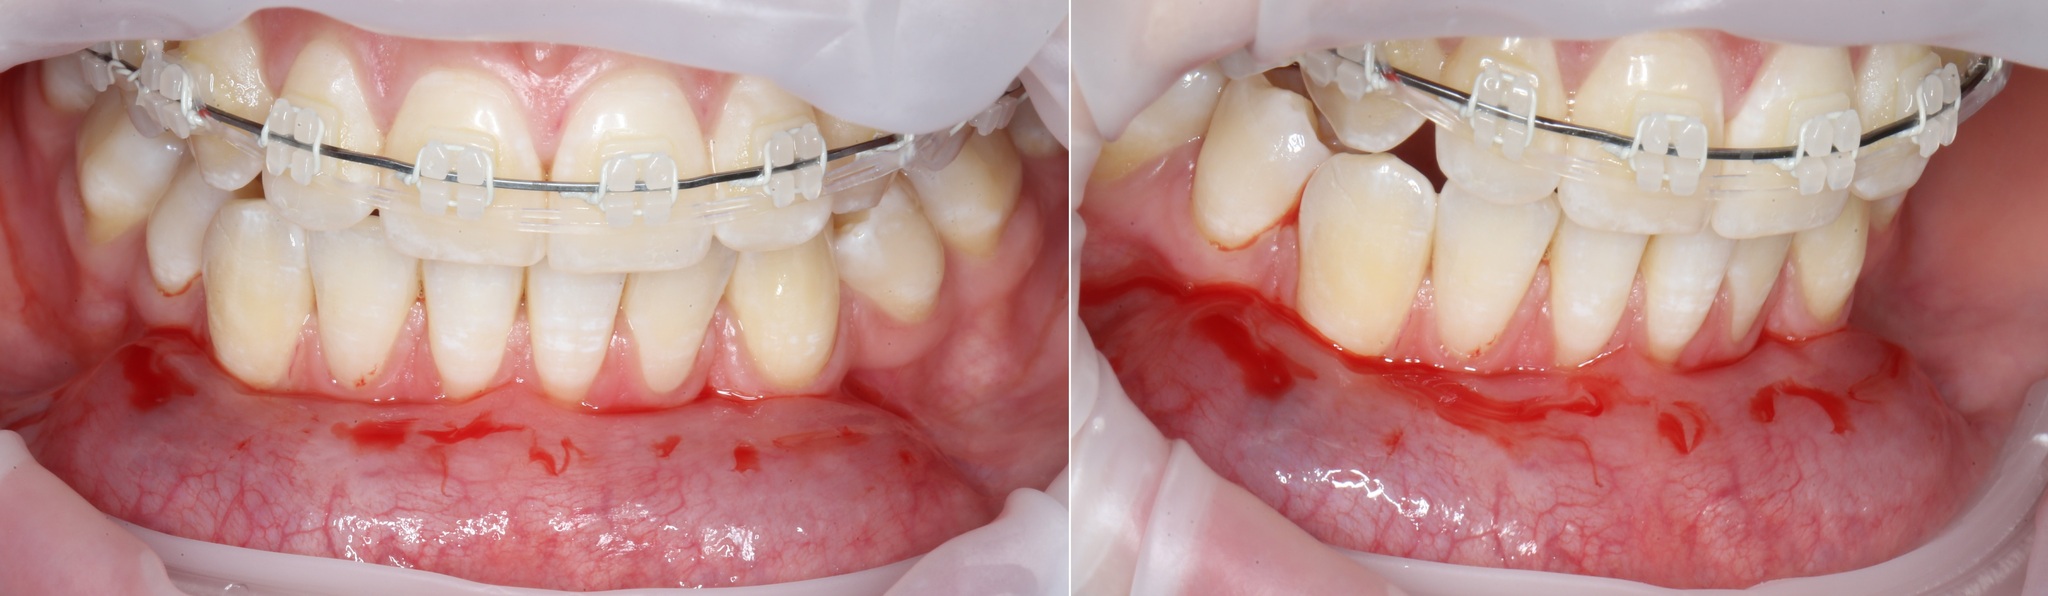

Это еще ладно, но если ничего не делать, то корни могут оголиться и так:

И даже так:

Во втором случае потеря двух центральных резцов – вопрос времени. Они уже подвижны.